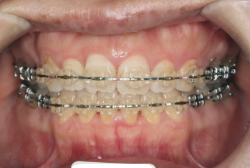

「歯並びの凸凹を直したい」という主訴で来院したケースです。診断の結果、たしかに「叢生」という隙間が足りないと言うことが原因の凸凹症例でした。

しかし、それ以上に問題なのは「前歯の噛み合い方が深すぎる」という症状で、初診の歯の正面写真を見ると下の前歯が全く見えません。こういう症状を矯正学では「過蓋咬合(かがいこうごう)」と言います。過蓋咬合を放置すると、将来的に顎関節に悪影響を与えるとされており、顎関節症の原因因子の一つです。また下の前歯の先端が、上の前歯の裏側の歯茎と強く接触するため、歯周病の原因にもなります。

検査の結果、凸凹が軽症なため非抜歯で矯正すること可能と判断、マルチブラケット装置にて治療しました。治療後は歯並びが綺麗になっただけでなく、噛み合わせ的にも正しい状態が確立しています。